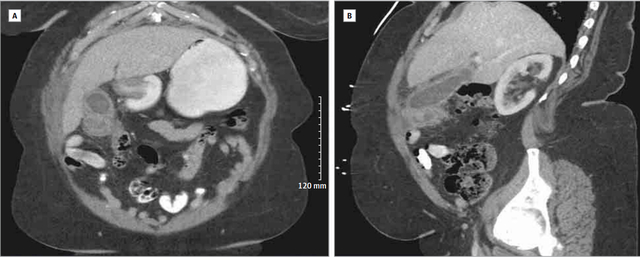

近期,Beteck 教授等在 JAMA Surgery 杂志上发表了一例关于特殊胆囊炎的病例报道。 图 1 CT 扫描的冠状面(A)和矢状面(B)显示胆囊底部有一软组织肿物 你的诊断是? A、急性胆囊炎 B、黄色肉芽肿性胆囊炎 C、胆囊癌 D、胆囊腺肌瘤 答案:B、黄色肉芽肿性胆囊炎 讨论 鉴于 CT 上可见胆囊底部有一 5 cm 的肿物,曾考虑过胆囊癌。术中超声探查显示:肝脏深部肿物、胆囊壁炎性浸润并伴有结石及软组织肿物。患者随后接受了开腹胆囊切除、部分肝脏切除。可见胆囊底部有一质硬结石,考虑可有癌变。横结肠和大网膜的部分与胆囊底部粘连。仔细分离结肠,切除部分大网膜。漏斗和胆囊管无炎症浸润,但有一 2 cm 结石。 术中病理显示良性病变。最终病理提示:胆囊周围胆汁外渗并伴有慢性黄色瘤浸润。确诊黄色肉芽肿性胆囊炎(XGC)的诊断(图 2)。 图 2 切除标本的镜下表现 黄色肉芽肿性胆囊炎是一种慢性的胆囊炎,其特征为不对称胆囊壁的严重炎性浸润,一般没有胆囊周围液体积聚。长期的慢性炎症使得胆囊与周围脏器形成粘连,并可能导致瘘管和狭窄的形成。虽然此病为一良性疾病,但是经常会误诊为胆囊癌。有报道指出约有 0.7%-13.2% 患者的胆囊有炎症浸润。